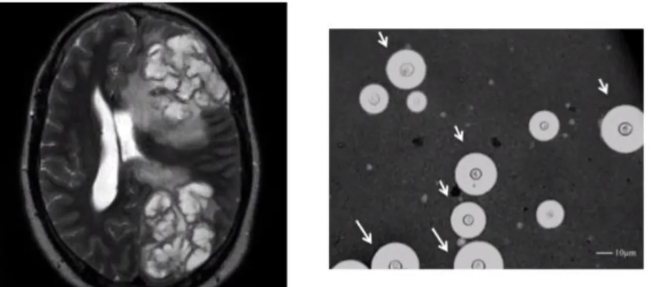

Cuál es la principal causa de meningitis por micosis?

El cryptococo

Enfermedad definitoria de SIDA a causa del cryptococo

Diseminación a SNC-meningitis

• Punción de LCR: Uso de tinta china para ver todo negro y la cápsula color blanco en el microscopio